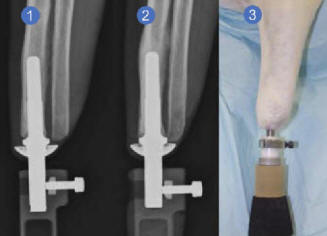

Sajnos még magas is a protézis funkciója nem mindig nyújtja a beteget a korábban birtokolt mobilitása. A szenzáció mellett az idegen alany gyakran figyelemelterelésként működik, vagy még egy visszataszító tényező, amely nem teszi lehetővé az észlelést protézis, mint az elveszett kar vagy láb teljes pótlása. az ezt azonban az intraseous technológia javíthatja transzkután amputációs protézis “(ITAP), utalva radikálisan eltérő megközelítés a protetika alapelveiről. együtt – a Londoni Egyetem és a A Nemzeti Királyi Ortopéd Kórház volt Kialakítottuk az egyedi lábprotezis modelljét. övé megkülönböztető jellemzője a kiválasztott csatlakoztatási módszer. Ahelyett, hogy műanyag lábat fektetne volna rá, rögzítse test amputáció, ITAP felépítés felhasználásával speciálisan tervezett fém elem kerül beültetésre a bőrön keresztül, ezáltal közvetlenül csatlakoztatva a protézist emberi csont.

Fotók nyílt forrásból Meg kell jegyezni, hogy azonnal megszólalt az implantátum as a kapcsolat a mű végtag, a csont és a lágy között a szövetek egyáltalán nem újdonságok. A projekt szerzői azonban lényegében elkészítette a fémimplantátum modelljét annak gyorsasága érdekében adaptáció a testben. Idén júliusban került sor az első kiválasztásra. emberek, akik ezt megtudják a gyakorlati tesztek során előnyei, tulajdonságai, valamint lehetséges hátrányai a protézis benyújtott változata. A rendelkezésre álló információk szerint erre pillanat már amputee 20 acél új mű lábtartók. Az ITAP implantátumok kényelme megerősíti Mark O’Leary, aki a tulajdonos lett vissza 2008-ban. Azt mondta, hogy olyan az elveszett végtag visszajött, és teljes mértékben érezte. Ennek alátámasztására O’Leary protetikus lábával sikerült meghódítania Kilimandzsarót és sokan mást más hegycsúcsok. Az első húsz beteg között aki tökéletes és fejlett technikai tapasztalatokat fog megtapasztalni tervmodell, Mark O’Leary már ebben a szakaszban szokatlanul megjegyezte valódi szenzációk mozgás közben. Az elutasítás elkerülése érdekében idegen anyag organizmusa, fejlesztők létrehozásakor az implantátum kihasználta a szerkezet jellemzõit … szarvát szarvas. Ennek a formációnak egyedi porózus szerkezete van, amelyet a tudósok vett alapul. Az ötlet fogalma: úgy, hogy a bőr sejtjei összeolvadnak egy idegen testtel, behatolva pórusokat analógia útján, mint a szarvas szarvak esetén. Készítette: a pecsétszöveteknek lyukakat kell kitölteniük és akadályozniuk kell baktériumfertőzések kialakulását, és megbízhatóan segítenek rögzítse a szerkezetet természetes módon. Számos ellenére olyan előnyök, mint a fájdalmas irritáció hiánya a helyén – a hagyományos protézis és a lábak ízületei súrlódás miatt, és – szintén kidolgozta a legmagasabb szintű visszajelzéseket ITAP láb és ember, a technológiának vannak hátrányai. tovább Lényegében egy ilyen protézis egyszeri és végleges jelentést jelent telepítést. A tulajdonos egyszerűen nem lesz képes önállóan eltávolítani tervezni.